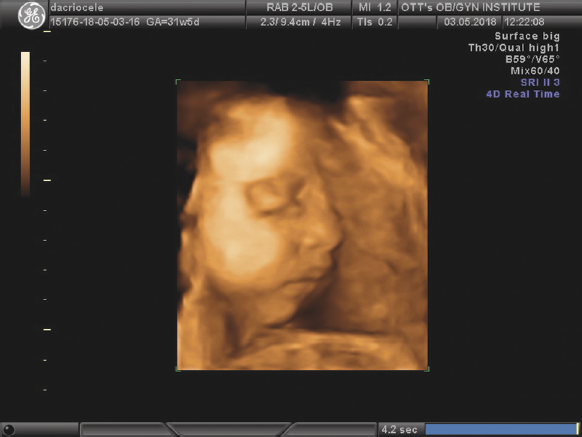

Рис. 4. Дакриоцеле, 31 неделя беременности